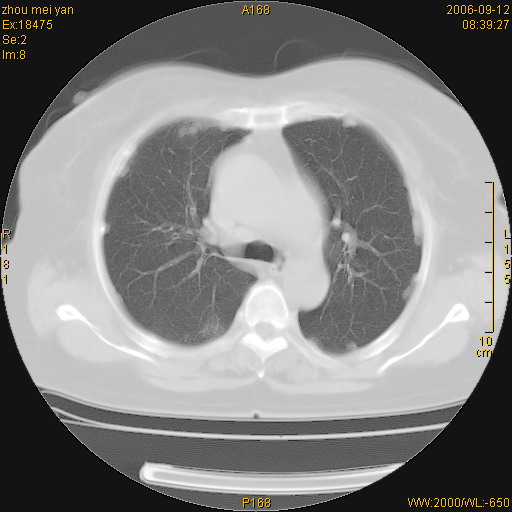

患者、女、55岁。因心率失常住院检查ct发现胸部多发结节。腹部b超肝、胆、胰、脾、肾、子宫附件未见异常。无结核病史,无粉尘接触史。请大家来会诊。谢谢!

病变位于胸膜,多发结节,边界清楚,内见小结节状钙化。其它未见异常。

双侧胸膜多发结节,形态不规则,边缘较清楚,每一个结节中心似乎都有钙化点的特征,与胸膜广基相切。临床无结核病史,无粉尘接触史。

影像表现十分有特点:双侧肋胸膜及膈胸膜广泛散在分布大小在2至6mm左右,较大病灶中心可见钙化。

双侧肋胸膜及膈胸膜广泛散在分布大小不等结节影,较大病灶中心可见钙化。

如果有类风湿性心脏病,就要高度怀疑是:类风湿性胸膜结节。疑问:病人血沉不快,是不是类风湿稳定期?另外病人肺内无明显纤维化改变,肺野内清晰,不符合类风湿肺内改变。